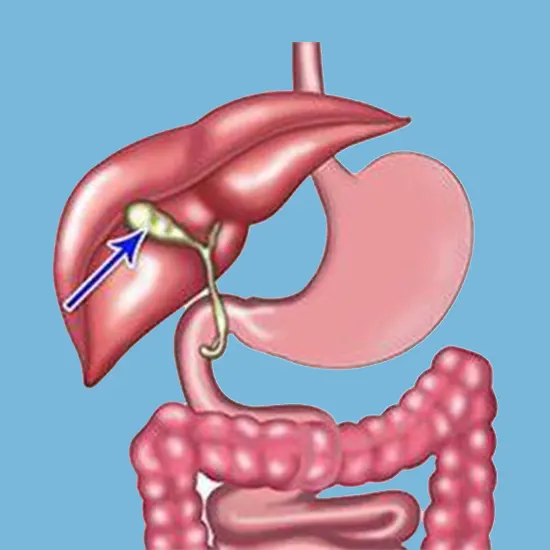

Less invasive treatments : If gallbladder cancer is detected early, less invasive treatments may be possible. For example, if the cancer is caught early enough, it may be possible to remove the gallbladder through a minimally invasive procedure known as laparoscopic surgery.